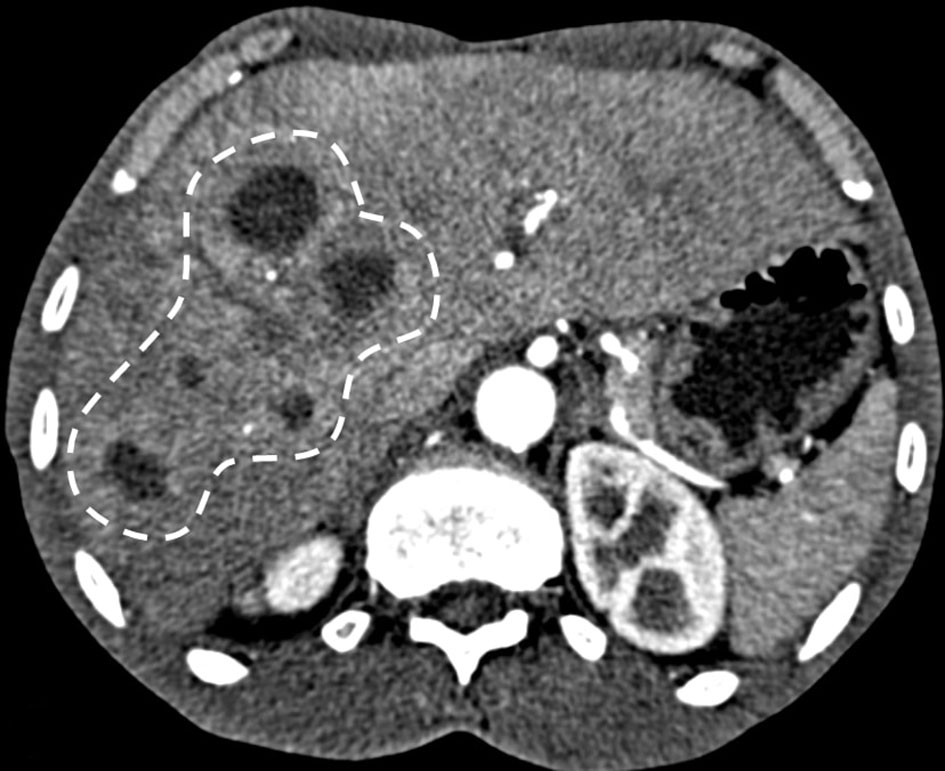

A 63-year-old healthy African-American male presented with a 4-day history of food aversion, subjective fevers, chills, chest and abdominal pain. His past medical history was significant for remote history of tobacco and cocaine use and was negative for diabetes mellitus or other medical illnesses. He was not on any prescription or over-the-counter medications. On presentation, he was found to have a fever of 38.3°C, but he was hemodynamically stable. A detailed physical exam was noted for poor dentition but otherwise was unremarkable. Laboratory testing revealed a white cell count of 22.4 × 109/L, aspartate aminotransferase of 93 units/L, alanine aminotransferase of 110 units/L and total bilirubin of 1.2 mg/dL. Contrasted computed tomography of the chest, abdomen and pelvis revealed multiple indeterminate hypo-attenuating lesions throughout the liver (Fig. 1). Further imaging with an abdominal sonogram identified multiple complex hypoechoic foci throughout the liver. Magnetic resonance imaging of the abdomen demonstrated multiple cystic lesions with enhancing internal septations and marked diffusion restriction. The largest lesion measured 4.5 cm × 4.1 cm × 3.8 cm (Fig. 2).

![]() Click for large image | Figure 1. CT with contrast showing multiple hypoattenuating lesions in the liver (dashed line). |